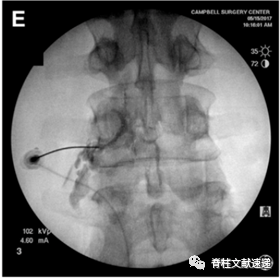

1.1俯卧位,常规消毒,定位,正位时调整C臂机,使目标椎间隙平行(上图A)

1.2.穿刺的靶点是椎体后缘、椎弓根外下缘、出口根上方,见蓝点(上图B)。

1.3.透视正位,针尖位于椎弓根的外下缘(上图C),透视侧位,针尖紧贴椎弓根下方(上图D)。

1.4.穿刺位置良好后,抽吸测试,若无血液和脑脊液,可行造影剂观察(上图E),再行局麻药物注入,观察症状缓解情况。